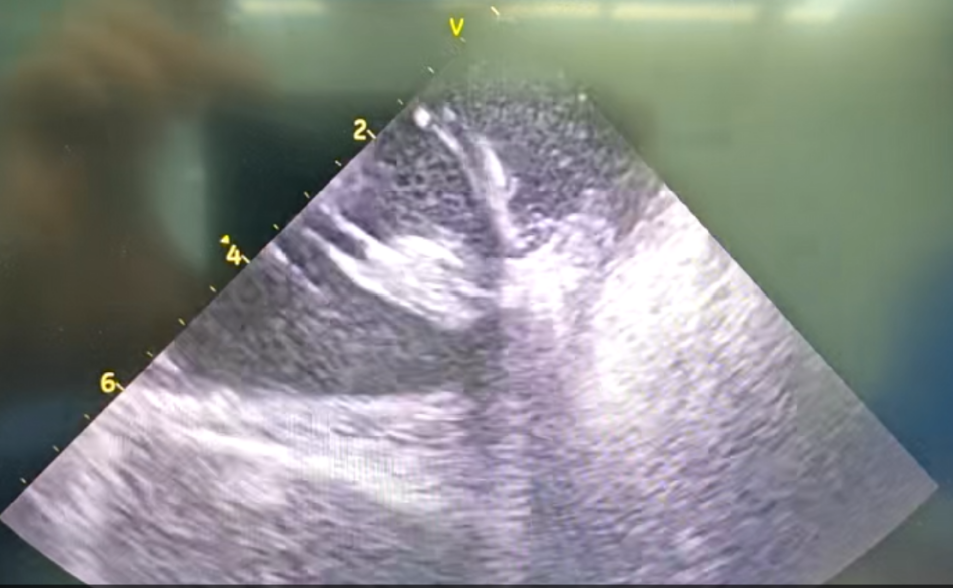

术中自发多种形态室速

干穿心包进入外膜标测

部分内膜室速靶点电位

王林林主任医师谨慎操作,成功进入心外膜达到病变位置。术中,患者反复自发多形态室速,且转为室扑,同时出现血流动力学不稳定,需多次电除颤方能终止发作,标测难度极大。这就要求医疗团队必须在有限的标测时间内精准定位室速消融靶点,并结合心内外膜基质特征制定消融策略。经针对性消融后,患者未再自发室速,且室性早搏转为单一形态,经判定为右心室乳头肌来源,随即予以一并消融。术后经心室程序电刺激验证,室速未再被诱发。